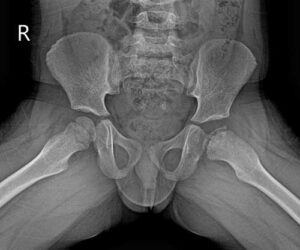

After discussing your child’s symptoms and medical history, your doctor will conduct a thorough physical examination and take x rays of the hip. Usually 1-2 x rays are adequate to make the diagnosis of Perthes disease, but sometimes confirmation diagnosis or treatment planning may need MRI scan of hips.

A child with Perthes can expect to have several x-rays taken periodically over the course of treatment. As the condition progresses, x-rays often look worse before gradual improvement is seen.